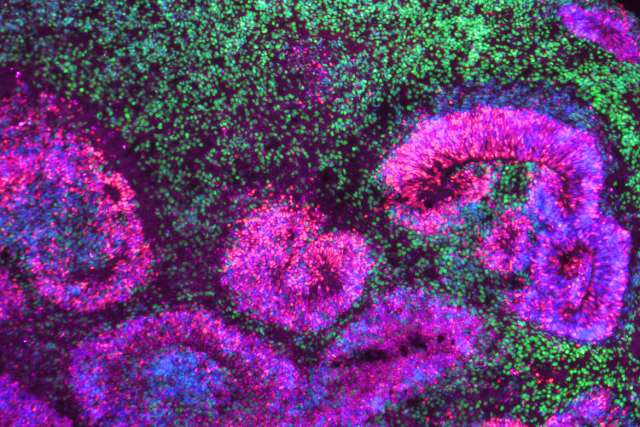

Microscopy image of a cortical organoid, a stem cell-derived model that mimics the developing human brain. The circular rosettes are clusters of neural stem cells giving rise to neurons, shown in green.

Microscopy image of a cortical organoid, a stem cell-derived model that mimics the developing human brain. The circular rosettes are clusters of neural stem cells giving rise to neurons, shown in green. | Credit: Jose Soto/Bhaduri Lab